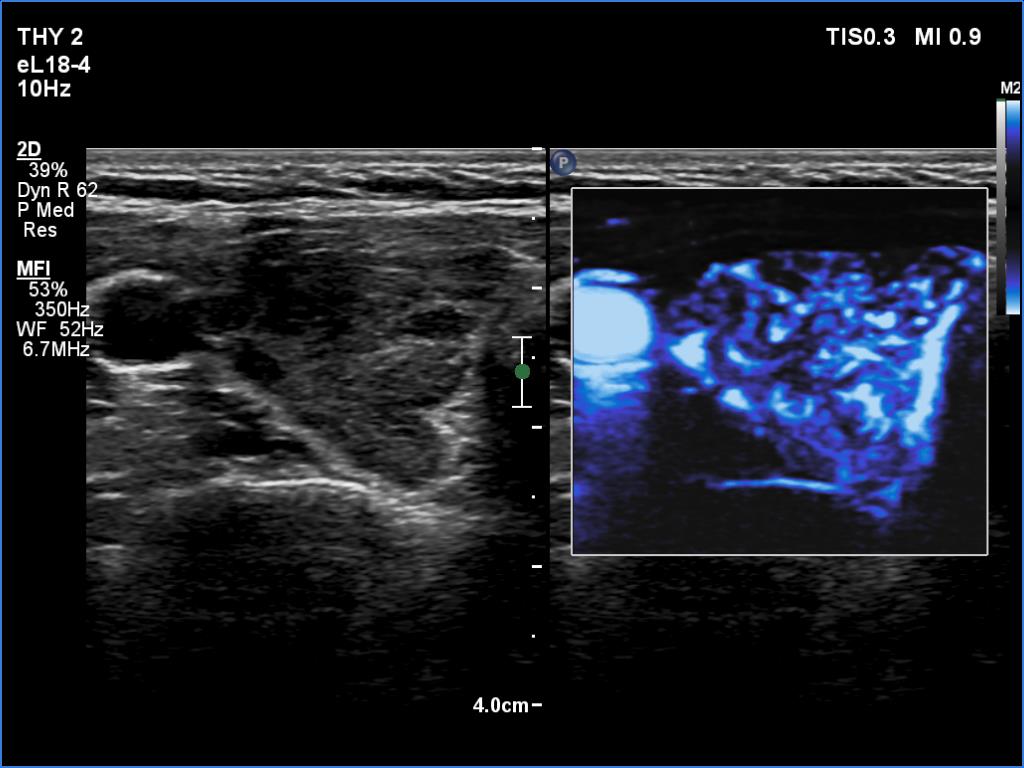

Right lobe, longitudinal scan

Right lobe, transverse view, microflow imaging. The vascularization is increased.